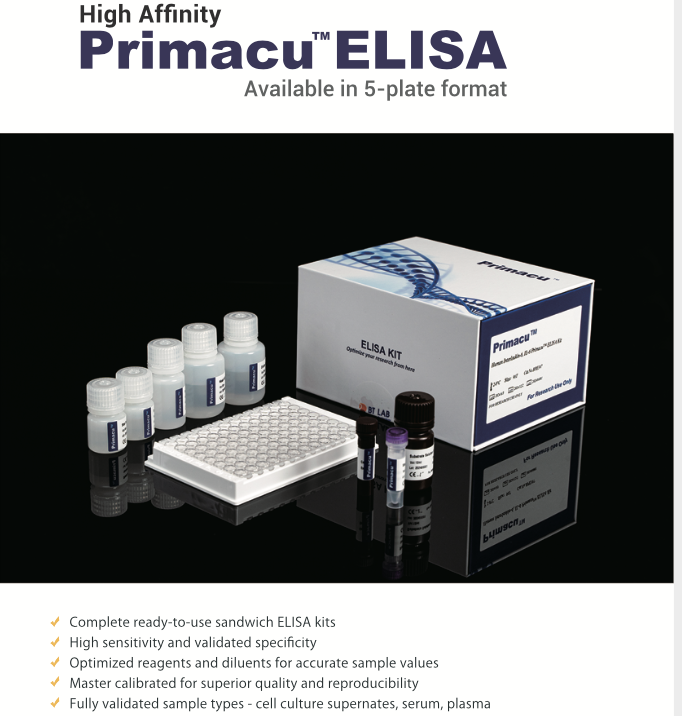

Kits